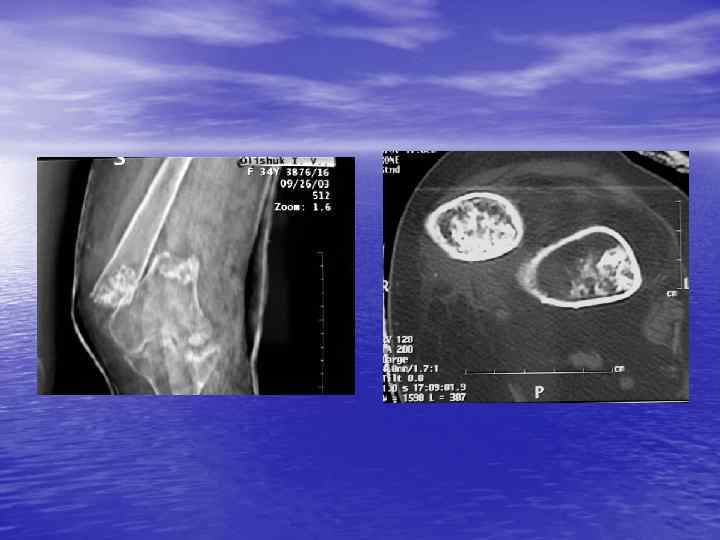

Структурный анализ Оценка основных макроскопических признаков: - положение - форма - размеры - характер контуров и структур патологически измененных участков

Денситометрический анализ Определение основных видов патологических образований: - обызвествленных - мягкотканных - жидкостных - жиросодержащих - воздухсодержащих